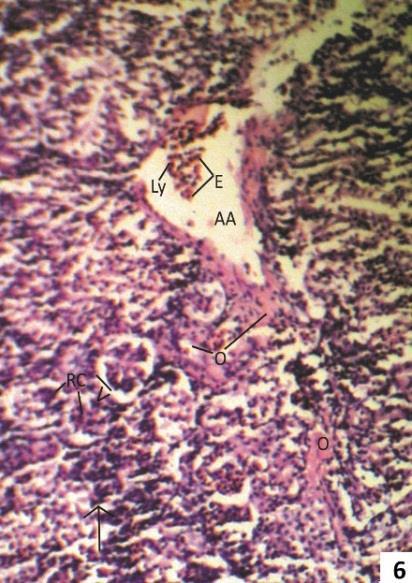

Fig. 5 & 6: Photomicrographs of transverse sections of kidney of one week 5.0 ppm arsenic treated (Group II) Clarias batrachus stained with Haemotoxyline &Eosin.

Fig. 6: Section showing beginning of metastatic calcification with marked fusion of glomeruli (arrow head), calcification of elastic lamina (arrow) and presence of lymphocyte (Ly) and eosinphils (E) in lumen of arcuate artery and oedematous fluid in peritubular space (PTS).

After one week treatment of 5.0 ppm As2O3 fish kidney showed widening of urinary space intermingling of visceral and parietal layer of Bowman’s capsule, and infiltration of lymphocytes, plasma cells and deposition of oedomatous fluid in peritubular space (Fig. 5). Massive metastatic calcification of glomeruli were also seen (Fig. 6).